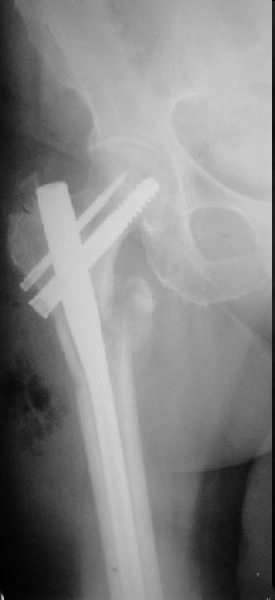

Это типичная проблема, вот аналогичный случай. Удалили, исправили, фиксировали другим PFN.

|

Все, что было написано по снимку со сломанным гвоздем, остается в силе. Чрезмерно латеральная точка введения, медиальное направление в центральном отломке. То есть варус не устранен, откуда все последующие проблемы. Как решать - уже написал. Конечно, есть и другие варианты реостеосинтеза (клинковая пластина, DHS, даже аппарат) - но тут вполне выполним все еще малоинвазивный реостеосинтез аналогичным гвоздем с исправлением ошибок.